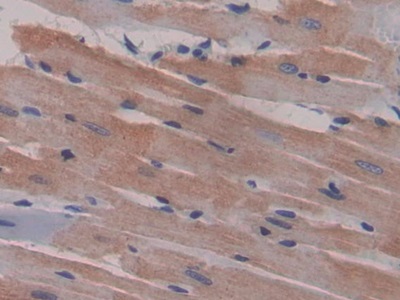

- ApplicationsIHC

The antibody is a rabbit polyclonal antibody raised against MIP1g. It has been selected for its ability to recognize MIP1g in immunohistochemical staining and western blotting.

Immunohistochemistry: 5-20µg/mL;

Optimal working dilutions must be determined by end user.